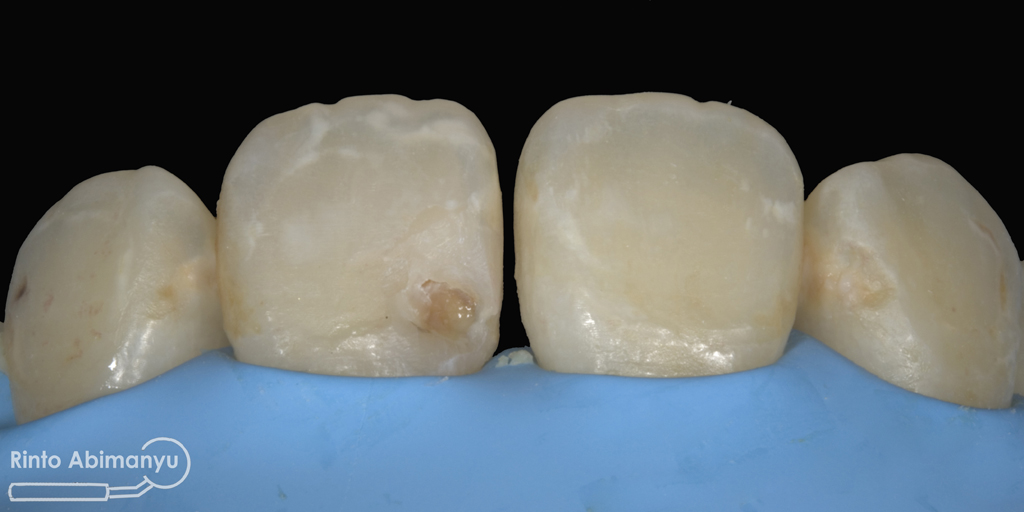

Pada pemeriksaan intra oral terlihat gigi 23 dan 24 mengalami karies dan cukup banyak sisa makanan terjebak disana…

Pertama saya lakukan anestesi infiltrasi dan kemudian memasang rubber dam untuk isolasi daerah kerja, dilanjutkan pembersihan karies dan pembukaan kamar pulpa.. Pada kasus ini pengerjaan dilakukan langsung pada dua gigi…

Setelah akses ke kamar pulpa didapat, lalur dirapihkan agar arah masuk file dapat lurus, maka selanjutnya adalah proses cleaning and shaping… Panjang kerja diukur menggunakan apex locator Root ZX mini (Morita) dan preparasi saluran akar menggunakan i3 Gold (Denjoy)… Irigasi memakai larutan NaOCl 5,25% dan diaktivasi menggunakan waterpik dan tip endoactivator…